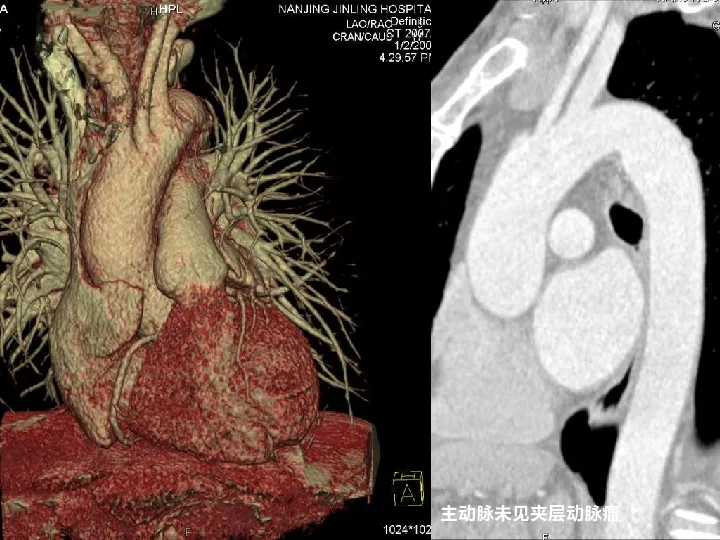

>【影像PPT】双源CT及其临床应用

【影像PPT】双源CT及其临床应用